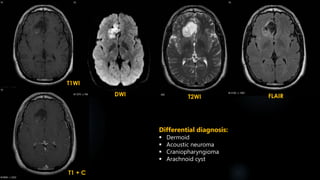

Epidermoid (contd.)

 Similar to CSF on T1 & T2

 High signal in case of white epidermoids

 Incomplete nulling on FLAIR

 DWI – Restriction

 No enhancement, Thin enhancement at the periphery

 25% may show rim enhancement

 White epidermoid – More protein and debris ---- high signal on T1 & CT.

T1 + C

T1WI

DWI T2WI FLAIR

Differential diagnosis:

 Dermoid

 Acoustic neuroma

 Craniopharyngioma

 Arachnoid cyst